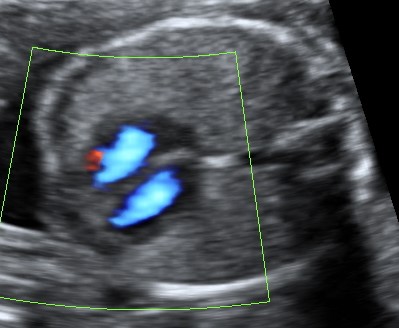

Ultraschall-Galerie